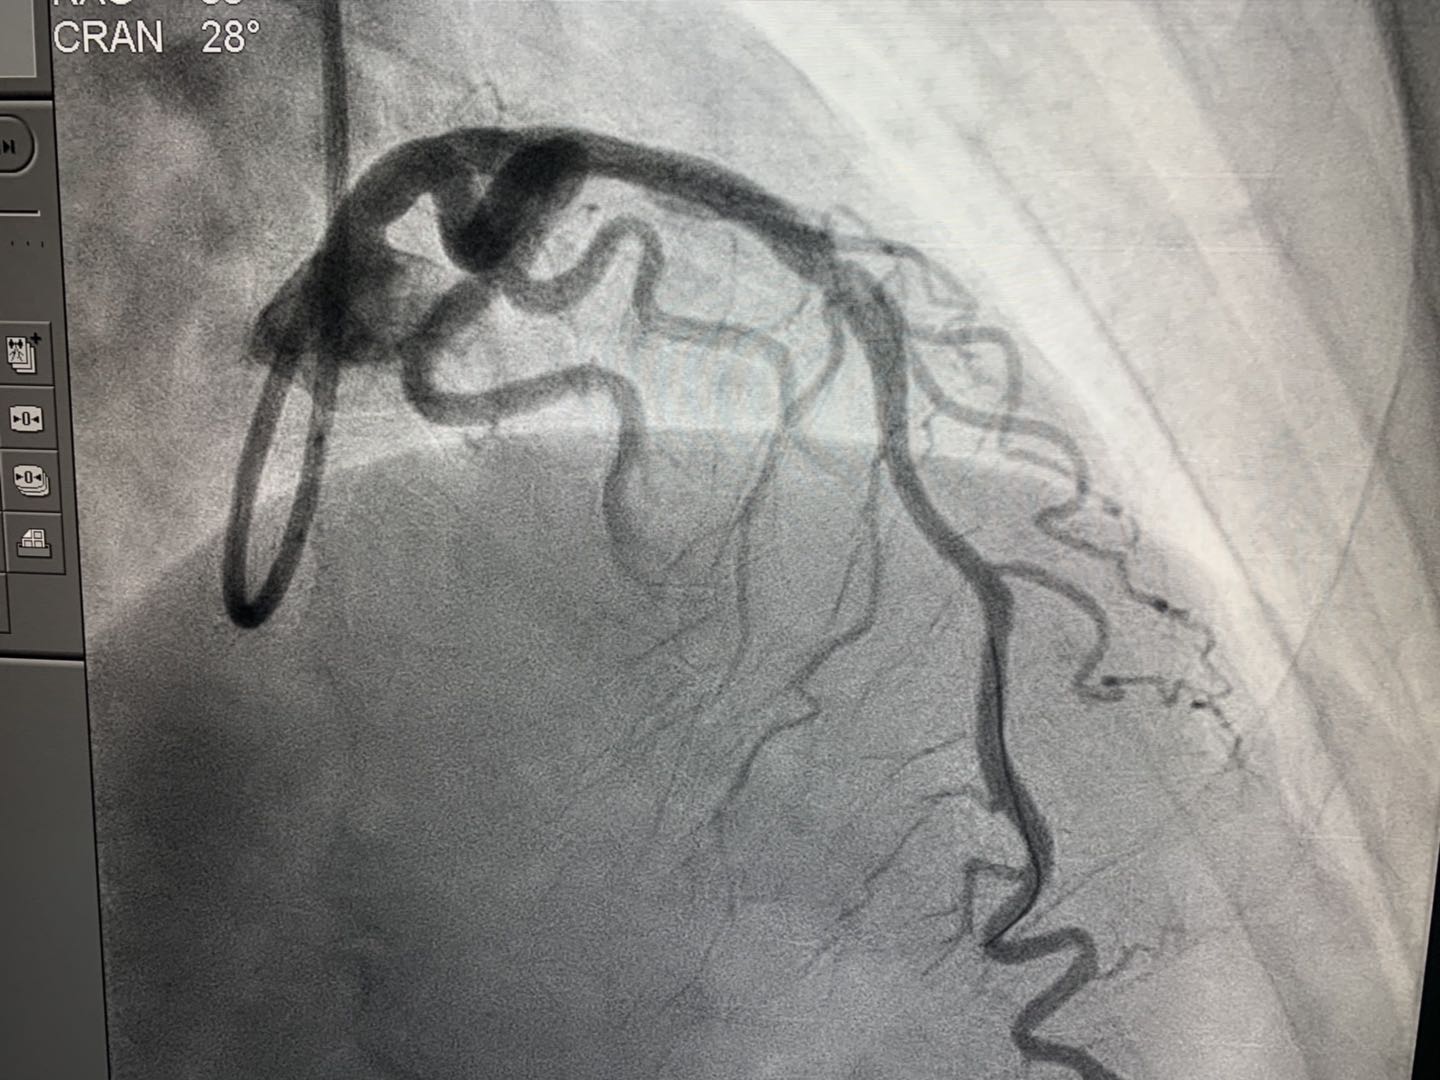

2019年4月16日,新疆首例生物可吸收心脏支架植入术在新疆医科大学附属中医医院(自治区中医医院)成功实施。医院心脏中心冠脉介入团队在武刚主任带领下,为一例50岁男性患者冠状动脉前降支近端成功植入NeoVas生物可吸收支架一枚。术中、术后采用光学相干断层扫描(OCT)对冠脉病变及植入支架进行评估。手术顺利,患者体征平稳。